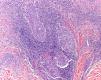

HistologyOn histopathology, the dermis was infiltrated by a lymphoproliferative process with a perivascular and periadnexal distribution and with minimal epidermal involvement (Fig. 2). The hair follicles presented a lymphoproliferative infiltrate, with the presence of mucin that stained intensely positive with Alcian blue at pH 2.5. Immunohistochemistry was positive for CD3 (Fig. 3), CD5, and CD7, with deletion of CD2 and partial deletion of CD4. The proliferating cells were negative for CD30, CD56, TIA-1, perforin, and granzyme B. Molecular study showed clonal rearrangement of the gamma chain of the T-cell receptor.

Histopathology usually shows a dermal infiltrate with a perivascular and adnexal distribution, with infiltration of the follicular epithelium by atypical lymphocytes of follicular size and with cerebriform nuclei. There may be associated follicular mucinosis, although this is not a constant finding, and syringotropism and even squamous syringometaplasia. Five different basic patterns are recognized: the classic pattern, with or without associated follicular mucinosis; the eosinophilic folliculitis-like pattern; the cystic pattern; the basaloid pattern; and the granulomatous pattern.4